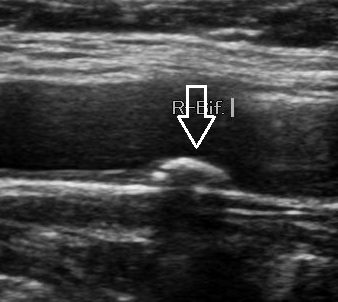

경동맥 초음파는 7MHz 이상의 선형 탐촉자를 사용해 경부 혈관의 내중막두께(IMT), 죽상경화반(플라크), 혈전, 박리, 협착 정도 등을 평가합니다.

경동맥 초음파는 목의 큰 동맥(총경동맥·내경동맥·외경동맥) 벽과 혈류를 실시간으로 확인하는 비침습적 검사입니다. 경동맥 초음파 검사로 알 수 있는 병은 대체로 심뇌혈관질환 위험이 의심되거나, 일과성허혈발작(TIA)·편마비 등 신경학적 증상이 있을 때, 또는 수술·시술 전후 평가에 표준적으로 활용됩니다. B-모드(흑백) 영상으로 혈관벽 두께와 플라크를 보고, 도플러로 혈류 속도와 방향을 정량화해 협착 정도를 평가합니다. 방사선 노출이 없고 10-20분 내외로 끝나며 반복 추적에 유리합니다.

2) 경동맥 협착증의 정량 평가

초음파 도플러로 최대수축기속도(PSV)와 분당 혈류를 측정해 협착을 등급화합니다. 전통적 SRU 기준에 따르면 ICA(내경동맥) PSV 125-230 cm/s는 50-69% 협착, 230 cm/s 이상이면 70% 이상 협착으로 판단합니다. 최근에는 50% 협착 문턱값을 PSV 180 cm/s로 높여 과대진단을 줄이려는 수정 기준도 확산되고 있습니다. 해석 시 플라크·내강 협소·ICA/CCA 비율 등을 종합합니다.